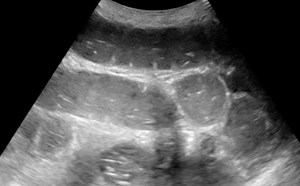

Although the FAST exam was initially presented as an assessment tool for trauma, it has proven effective at determining presence of intraperitoneal fluid in multiple disease states. The RUQ, or Morison’s pouch view has been determined to be highly sensitive in detecting the presence of intraperitoneal fluid in amounts as small as 200mL.18 (Video 14) The overall sensitivity of the exam is also improved by obtaining LUQ and pelvic views, (Video 15) as well as extending the RUQ/LUQ views to include each respective hemithorax.

Video 14. Image of RUQ view with intraperitoneal free fluid present

When evaluating undifferentiated hypotension, these views are useful as they may indicate hemorrhagic causes of shock due to occult trauma, abdominal aortic aneurysm (AAA) rupture, ectopic pregnancy, etc., as well as indicate whether a fluid collection may be a potential focus of infection such as in spontaneous bacterial peritonitis.